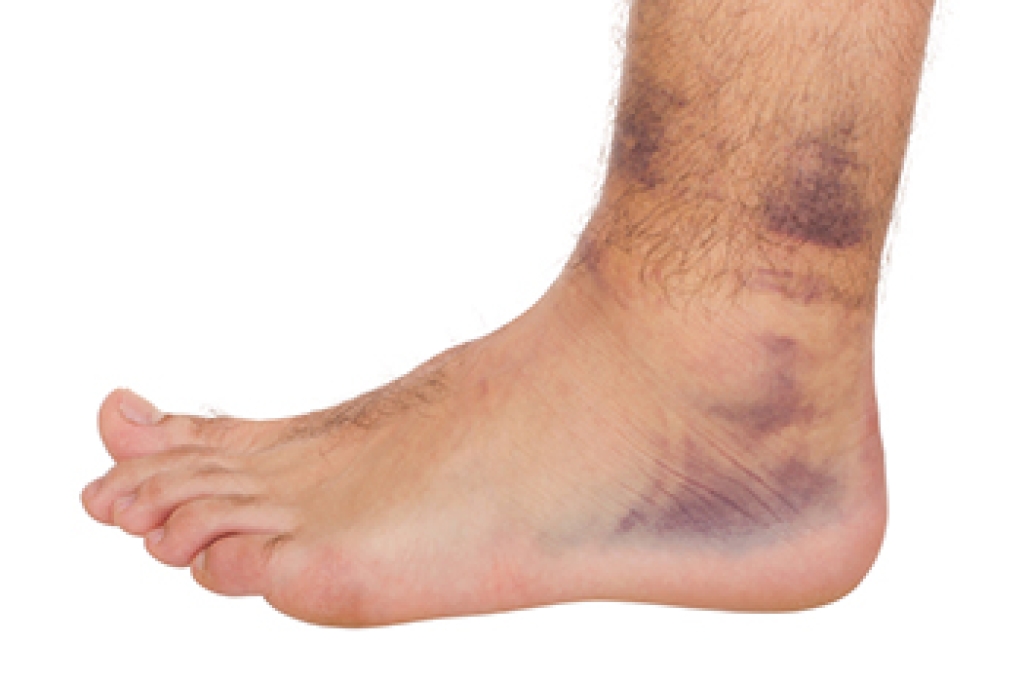

- Injury (from stress fractures, broken toe, foot, ankle, Achilles tendon ruptures, and sprains)

To figure out the cause of foot pain, podiatrists utilize several different methods. This can range from simple visual inspections and sensation tests to X-rays and MRI scans. Prior medical history, family medical history, and any recent physical traumatic events will all be taken into consideration for a proper diagnosis.